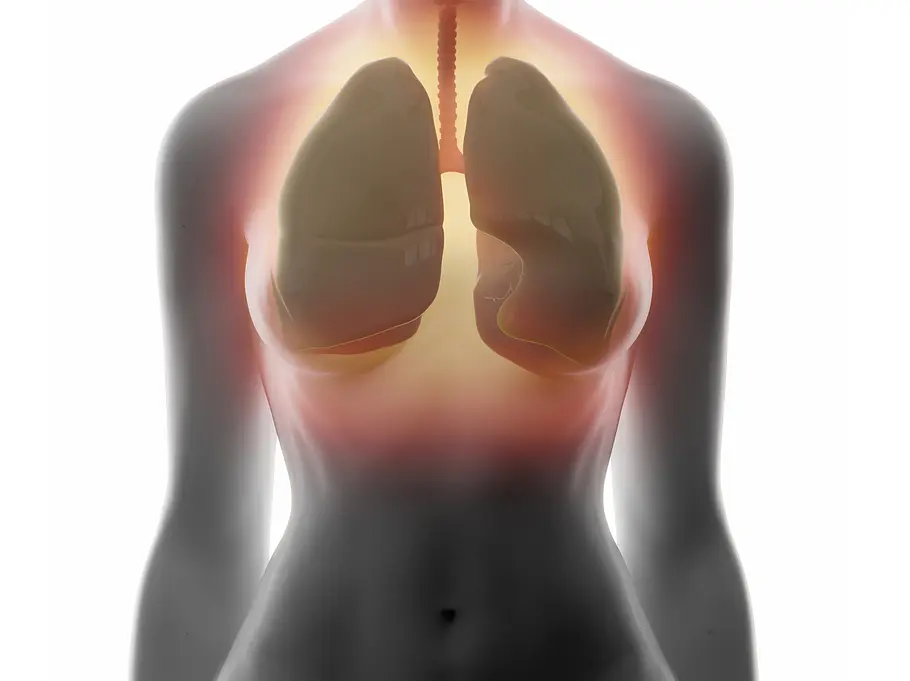

COPD: Viele leiden unter der unheilbaren Lungenkrankheit, ohne es zu wissen

Chronische Bronchitis gehört zu den häufigsten Erkrankungen. Eine frühe Diagnose kann den Krankheitsverlauf der unheilbaren Lungenkrankheit verlangsamen.

Die Abkürzung COPD steht für die englische Bezeichnung chronic obstructive pulmonary disease. Auf deutsch: chronisch-obstruktive Lungenkrankheit - also eine chronische Verengung der Atemwege.